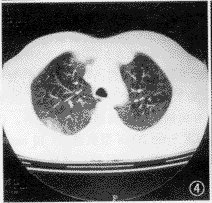

CT扫描,12例均有明显异常病灶显示。本组病例胸部CT表现包括:(1)小结节病灶 10例,结节影直径均在1 cm以下(范围0.5~1.0 cm),位居肺野外带胸膜下部(图1),其中8例小结节影周缘可见磨玻璃样密度的晕圈,即月晕征(图2,3)。(2)小斑片局灶性磨玻璃样密度影,在肺野外带浸润(图4),斑片与正常肺临界缘呈“小三角形”改变7例,部分在肺尖部散在,形似浸润型结核(图5)。(3)外带支气管血管束呈局灶性“Y”形增粗3例(图6)。上述小结节影、小斑片淡薄影均在两肺周边区域呈多灶性散在分布,没有大叶融合倾向。全组病例纵隔、肺门部未见肿大淋巴结。

图4 右上肺段斑片状磨玻璃样密度病灶